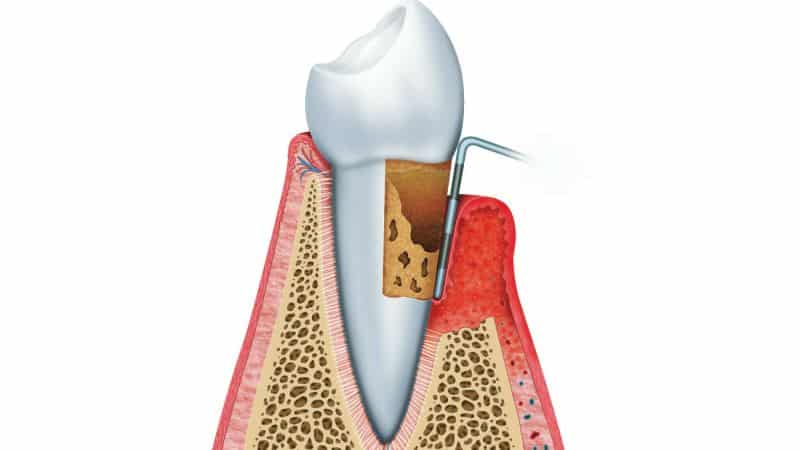

- Рассасывание периодонта. Воспаление достигает области соединения зуба с костью. Периодонт — это соединительная ткань, состоящая из мелких связок, которые обеспечивают надежное крепление зуба к челюстной кости. Воспалительный процесс разрушает эти связки и костную ткань, что приводит к образованию так называемых «пародонтальных карманов» (см. фото ниже). Эти карманы представляют собой пустоты, соответствующие объему разрушенного периодонта и месту его крепления к поврежденной кости. Пустоты заполняются заместительной тканью, микробами, патологическими жидкостями и гноем.

Крупные пустоты (от 4 мм и более), однажды возникшие, не исчезают самостоятельно, даже при эффективном лечении противовоспалительными средствами, антибиотиками и стоматологическими процедурами (лазерными, ультразвуковыми, гигиеническими и т.д.). Даже если вы запишетесь на процедуру удаления камней и налета, стоматолог не сможет с помощью стандартного оборудования очистить пародонтальные карманы. Если отложения остаются, воспаление продолжает существовать, что ведет к дальнейшему разрушению костной ткани и зубов.